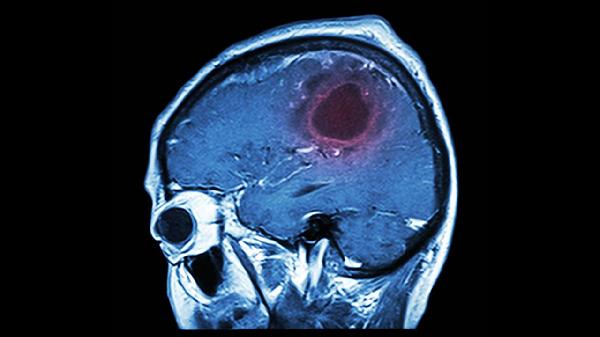

脑溢血后遗症主要包括运动功能障碍、语言障碍、认知功能减退、吞咽困难和情绪障碍等。脑溢血是指非外伤性脑实质内血管破裂引起的出血,可能导致脑组织损伤和神经功能缺损。